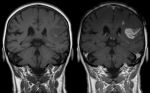

MRI of a stroke patientMost people who survive a stroke recover some degree of their motor, sensory and cognitive functions over the following months and years. This recovery is commonly believed to reflect a reorganisation of the central nervous system that occurs after brain damage. Now a new study, published in the February 2011 issue of Elsevier’s Cortex, sheds further light on the recovery process through its effect on language skills. Check the end of this report for a link to download the original study.

Odelia Elkana, from the Hebrew University, Jerusalem, and colleagues investigated the systematic patterns of reorganisation in the brain’s language functions, and their relation to linguistic performance, in patients recovering from childhood brain damage to the left hemisphere. They used functional MRI to detect patterns of brain activity while patients performed various linguistic tasks inside the scanner. The new study focused on a rare group of children whose brain damage had occurred after they had already developed language skills, but while the brain was still developing, and therefore most able to reorganise its language functions.